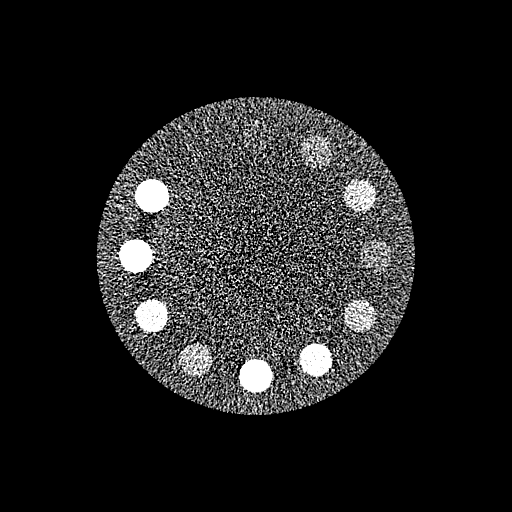

Conventional Physics-based Mono-Energetic Images

(20-cm cylindrical phantom)